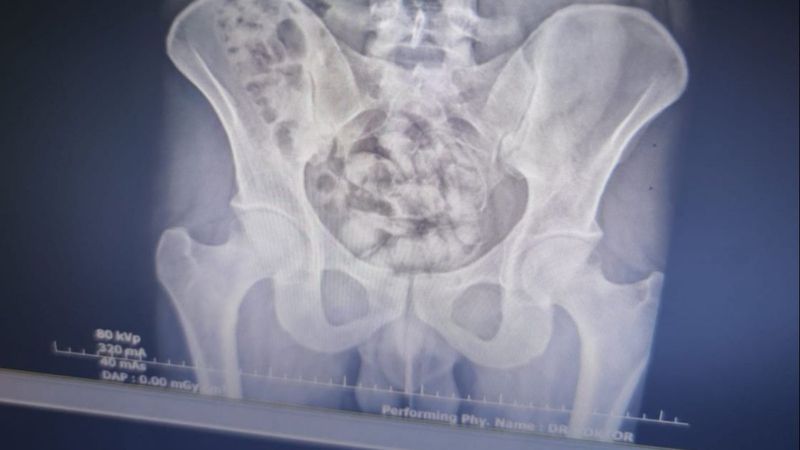

Uyuşturucu baskınlarında İran uyruklu S.Y.'nin röntgen filminde, midesinde 25 kapsül şeklinde uyuşturucu madde olduğu belirlendi.

Burada çekilen röntgen filminde, midesinde 25 kapsül şeklinde paketlenmiş halde 351 gr gelen metamfetamin olduğu tespit edildi.